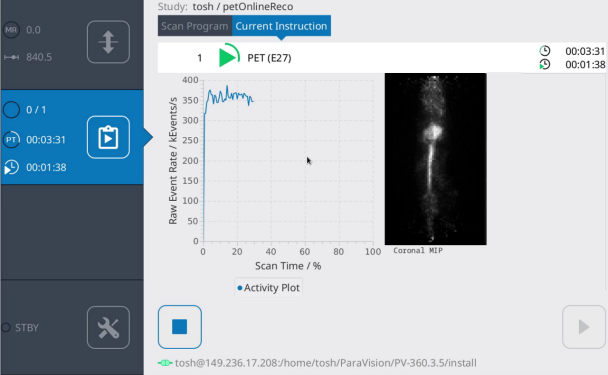

Efficient PET scanning

- Data is displayed on the touchscreen as well as in pre-defined single slices for fastest planning of further scans based on tracer biodistribution

- Real-time 3D display of tracer biodistribution during scanning

Touchscreen display of count rate evolution and MIP online reconstruction. Image Credit: Bruker BioSpin Group